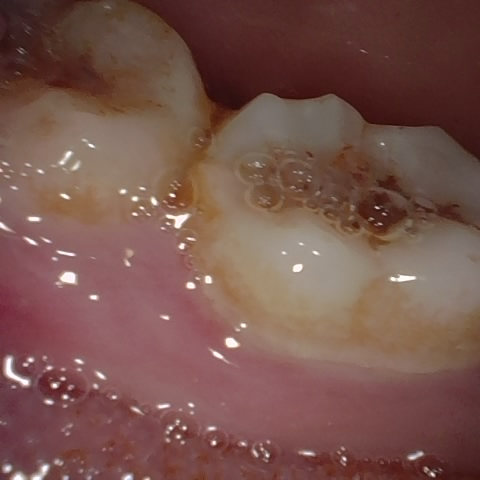

NHD11140

Annotated as "Good"

Original Image Rendering Image